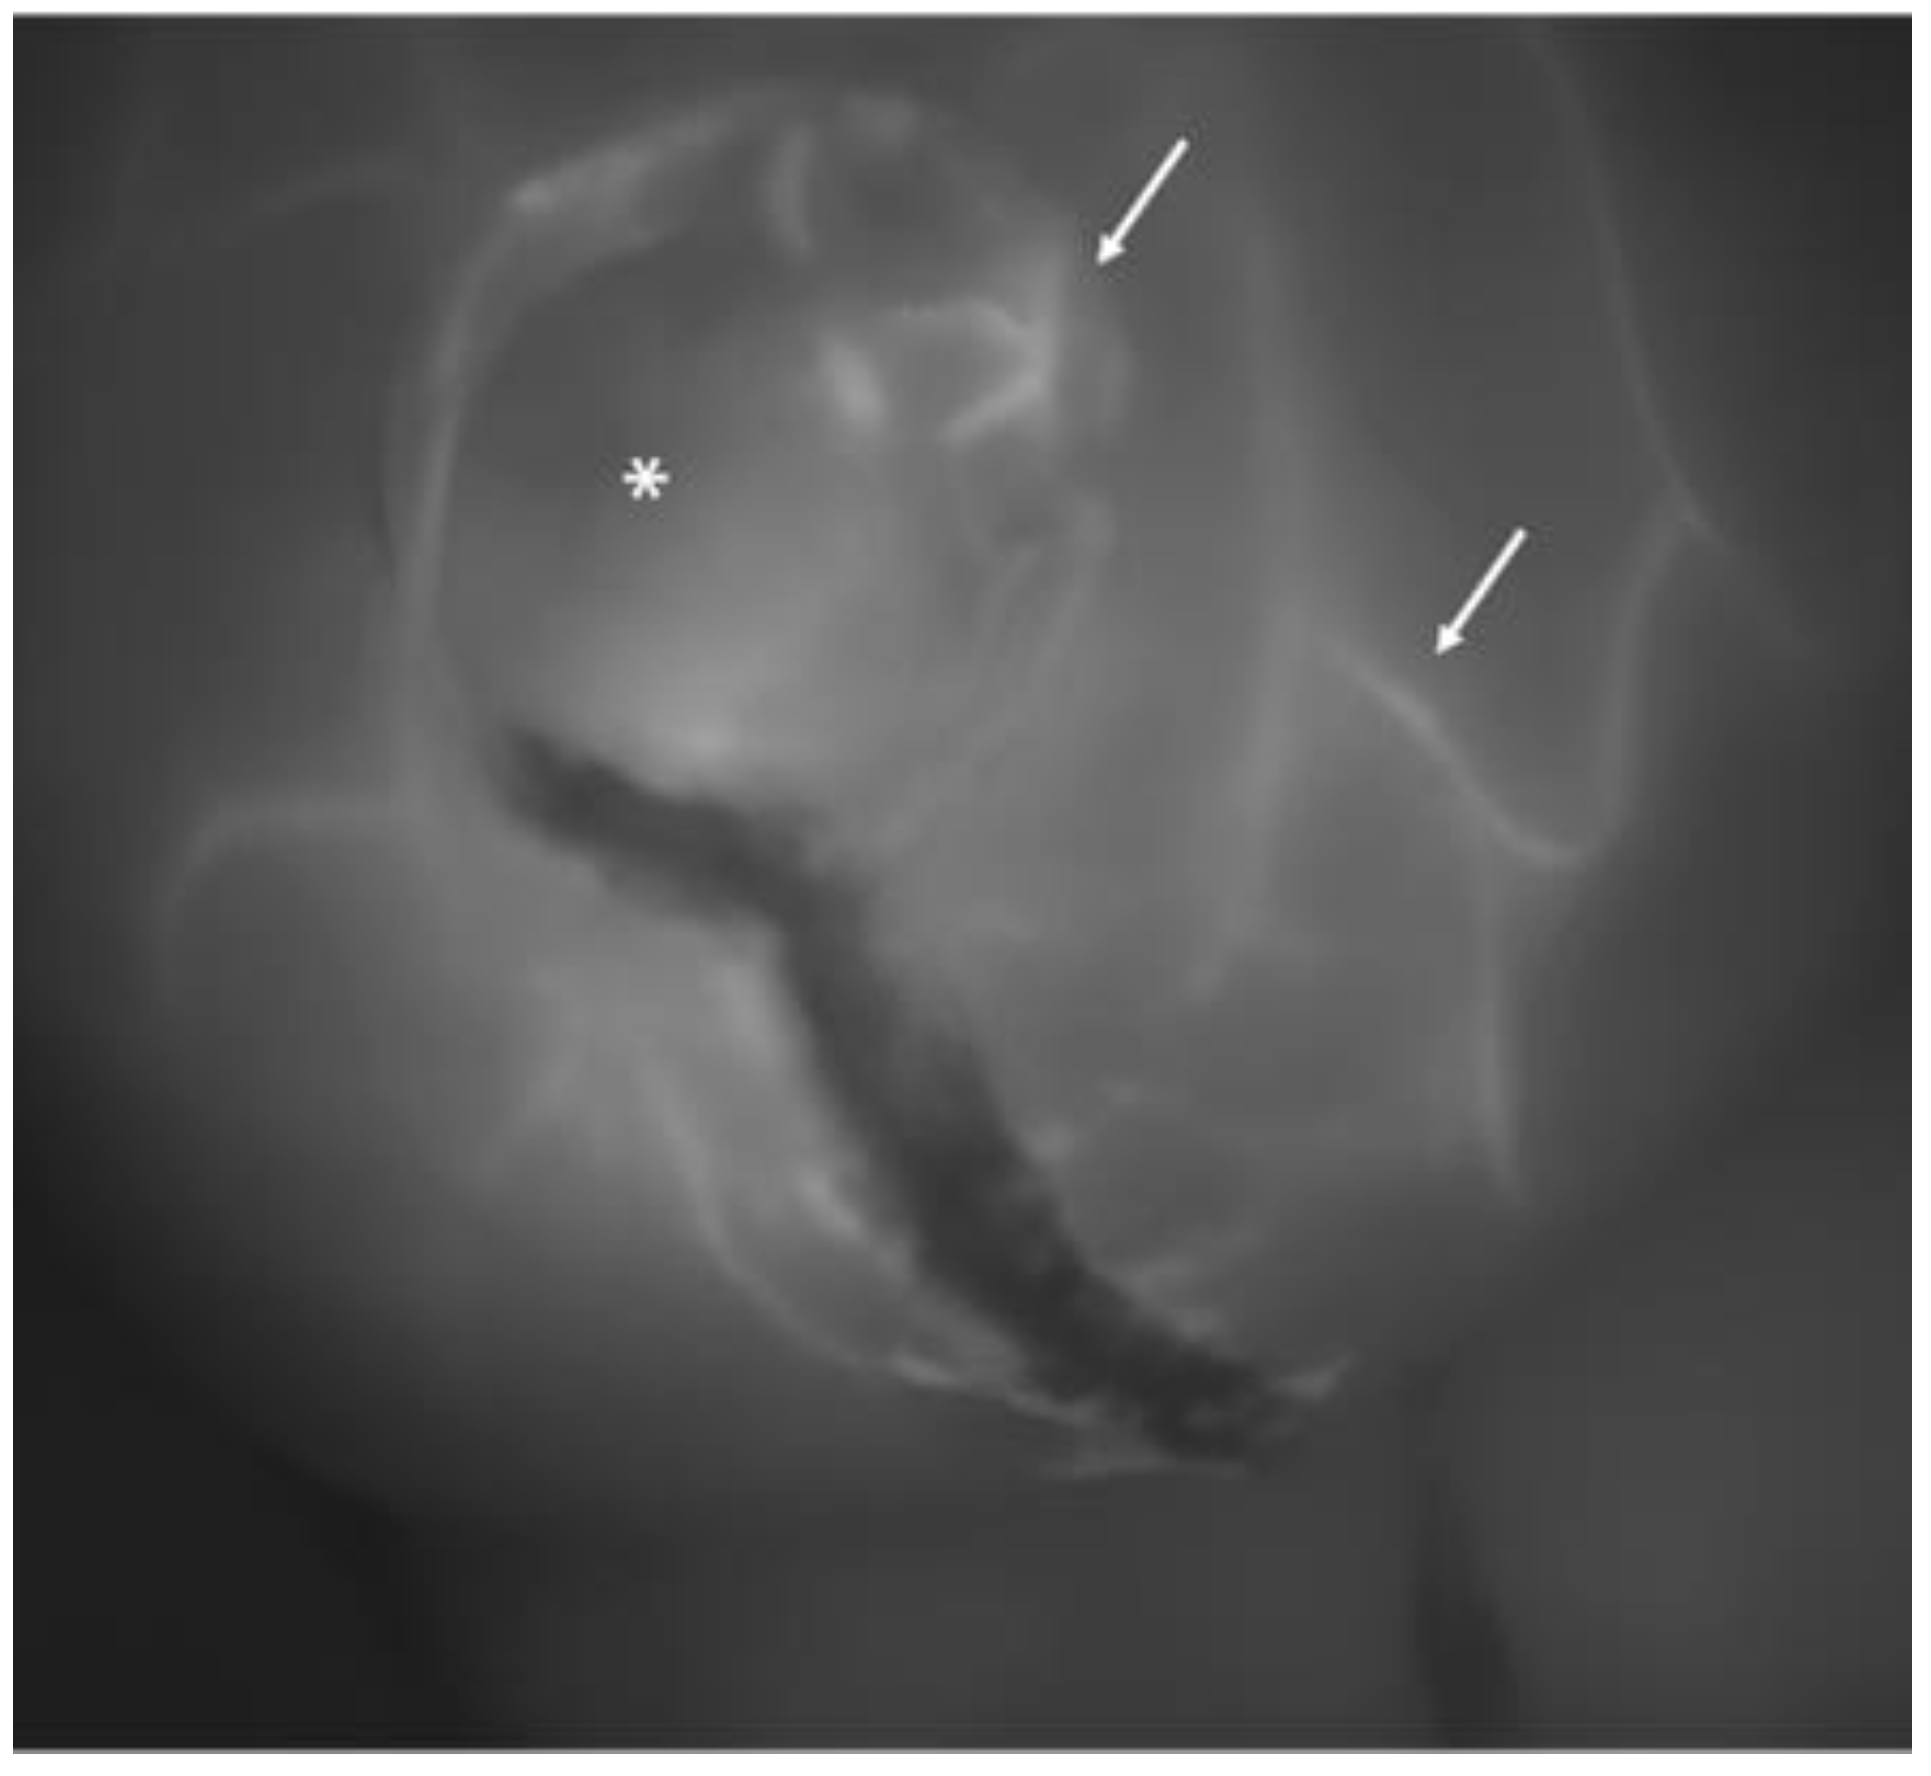

When the contrast permeated the skin layer through the capillary system, the grayscaled screen showed the radially extending pattern of vascularization from the perforator vessels (Figure 1 and Figure 2).

ICG angiography following mastectomy. The asterisk indicates the location of the nipple, and the white arrows highlight the small terminal branches of subcutaneous capillary vessels, exhibiting contrast enhancement and adequate perfusion.